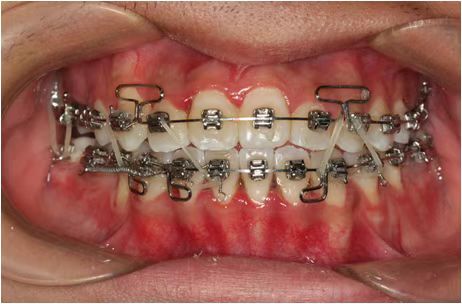

情况:不接受外科手术,在当地做了1年半的矫治,遇到困难无法进行。由外地正畸同行推荐来上海寻求非手术矫治的二手病例。武广增老师接收时的错合畸形情况,呈现严重的骨性反合偏合及侧方开合(图1-图10)。由于推荐其去口腔医院接受正颌外科手术遭到拒绝,武广增老师通过专业的检查、分析,制定一套详细的治疗计划,采用了磨牙推进器技术、武式辅弓技术等特色正畸手段获得明显效果(图2-1~图2-9)。治疗结束后也拍摄了相关照片(图3-1~图3-9)。

矫治效果

图2-2